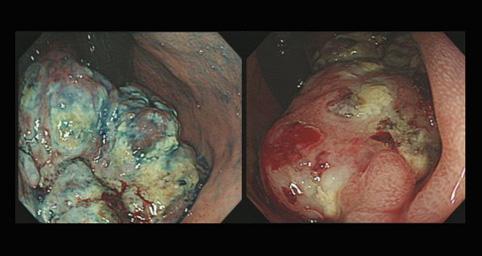

A case of gastrointestinal stromal tumor which developed at the esophagogastric junction area.

악성 비상피성종양/평활근육종

부위(장기별)

식도/하

내시경

1형(종괴형)/

종양의 최대경(밀리미터)